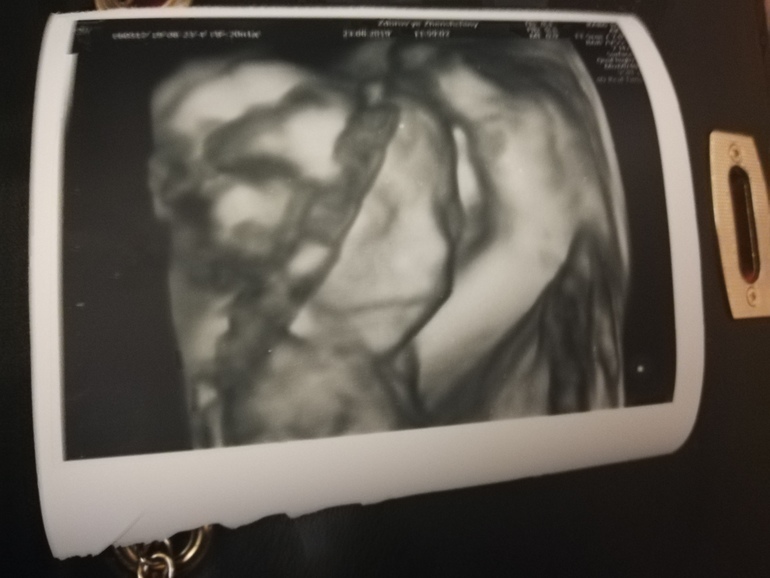

Вот моя 5 дочь, узи в 36 недель и 3 дня после родов😊. Главное что бы лежал удачно, тогда фото супер получаются